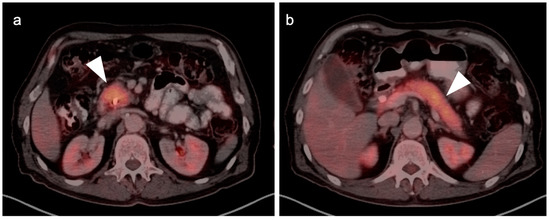

3. Gastrointestinal Stromal Tumor (GIST)